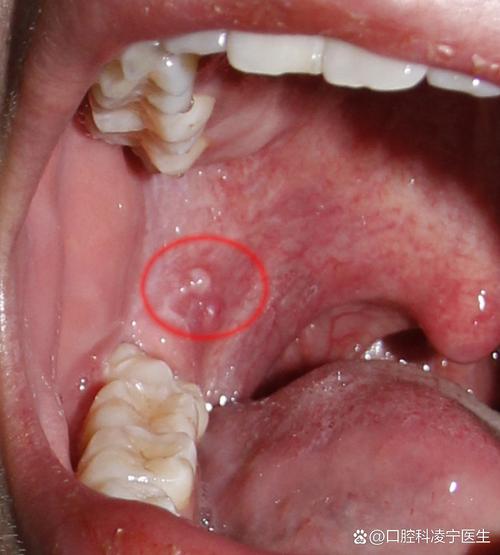

口腔咽喉感染hpv的症状 绝大多数HPV感染(包括口腔感染)是没有症状的,并且身体会自动在1-2年内清除病毒。 很多人可能感染了但自己完全不知道。(图片来源网络,侵删) 当HPV感染持续存在时,才可能导致出现症状或病变,以下是口腔咽喉HPV感染可能出现的主要症状,从最常见到相对罕见排列: 最常见且最典型的症状:口咽癌的警示信...

口腔白色东西是啥?要紧吗? 口腔内出现白色东西,可能由多种原因引起,有些是良性的,有些则需要警惕,请不要过于惊慌,但也不能掉以轻心。(图片来源网络,侵删) 下面我将根据白色东西的形态、位置和伴随症状,为您分析几种最常见的原因,并提供相应的建议。 可能性一:最常见的良性问题 口腔溃疡 (口疮) 外观:通常是圆形或椭圆形的溃疡,中...